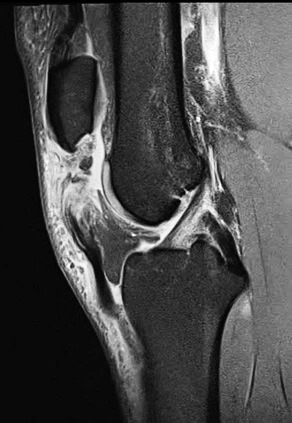

This is 74-year-old female, with a BMI of 33 kg/cm2, and multiple comorbidities (CHF, Arrhythmia, anxiety, 3 previous surgeries of the knee). She presented three months status post patellar tendon rupture, patellar fracture and dislocation. The patellar fracture was fixed with a wire, and in the radiograph you can see the anchor suture in the tibial tubercle area, the wire below the tubercle, within the gutters, and threaded above the patella. (Figure 8)

We removed the wire about six months following repair. At that time, she had ROM for 0-95 degrees. At six years out following repair she walks with no ambulatory aids and has full extension. (Figures 9, 10A-C)